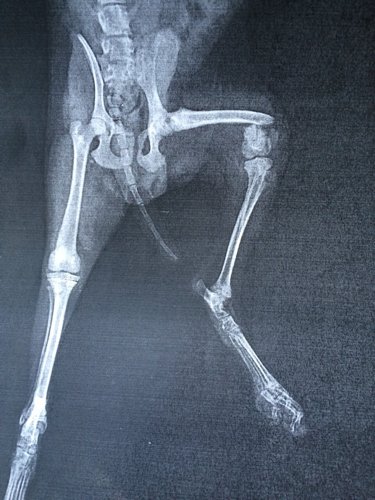

五个月小狗腿被踩断了,去了医院说这个位置要做内固定,手术成功率为一半,而且还要打全麻醉也有风险,到

五个月小狗腿被踩断了,去了医院说这个位置要做内固定,手术成功率为一半,而且还要打全麻醉也有风险,到底咋办呢?还有没有别的办法?知道的回答,谢了!

你好,看片子可确定是股骨远端骨折,这个位置只能安径院进行内细挤固定治疗,其它外固定等保守治团禁疗效果都不好。